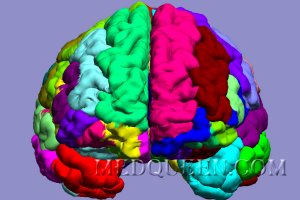

Головной мозгОсновная супраспинальная функция контроля двигательной системы осуществляется корой головного мозга, подкорковыми ганглиями, мозжечком и стволом головного мозга. Верхние (центральные) мотонейроны образуют часть двигательных путей от коры головного мозга до моторных ядер черепно-мозговых нервов и клеток передних рогов спинного мозга. Нижние (периферические) моторные нейроны состоят из клеток передних рогов спинного мозга и их аксонов.

Головной мозгОсновная супраспинальная функция контроля двигательной системы осуществляется корой головного мозга, подкорковыми ганглиями, мозжечком и стволом головного мозга. Верхние (центральные) мотонейроны образуют часть двигательных путей от коры головного мозга до моторных ядер черепно-мозговых нервов и клеток передних рогов спинного мозга. Нижние (периферические) моторные нейроны состоят из клеток передних рогов спинного мозга и их аксонов.

Моторная кора находится в предцентральной извилине, немного кпереди от ролландовой или центральной борозды (4 корковое поле; см статью «Кора Головного Мозга: Общие Сведения»). В предцентральной извилине сосредоточено четкое соматотопическое функционирование нейронов – моторный гомункулус Пенфилда с большей зоной, отвечающий за выполнение тонких движений губ, языка, кистей; и моторный гомункулус Пенфилда с меньшей зоной, отвечающий за движения конечностей и др (рисунок 1).

Рисунок 1. Моторные зоны коры головного мозга

Кроме 4 коркового поля мотонейроны также находятся в соседних кортикальных полях (в так называемой сенсомоторной области коры головного мозга). Так, медиальные участки премоторного 6 поля представляют собой вспомогательную двигательную зону коры мозга.